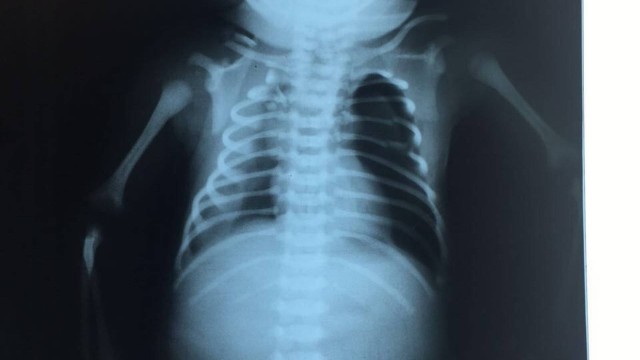

Raio-X de Arthur, que nasceu logo após ser baleado dentro da barriga de sua mãe, Claudineia dos Santos

A equipe médica responsável pelo atendimento do bebê baleado na barriga da mãe na última sexta-feira disse que o quadro de paraplegia do pequeno Arthur pode ser revertido. Os médicos se reuniram nesta segunda-feira com o secretário de saúde de Duque de Caxias para uma coletiva de imprensa. O bebê foi atingido durante um tiroteio na Favela do Lixão e permanece em estado grave.